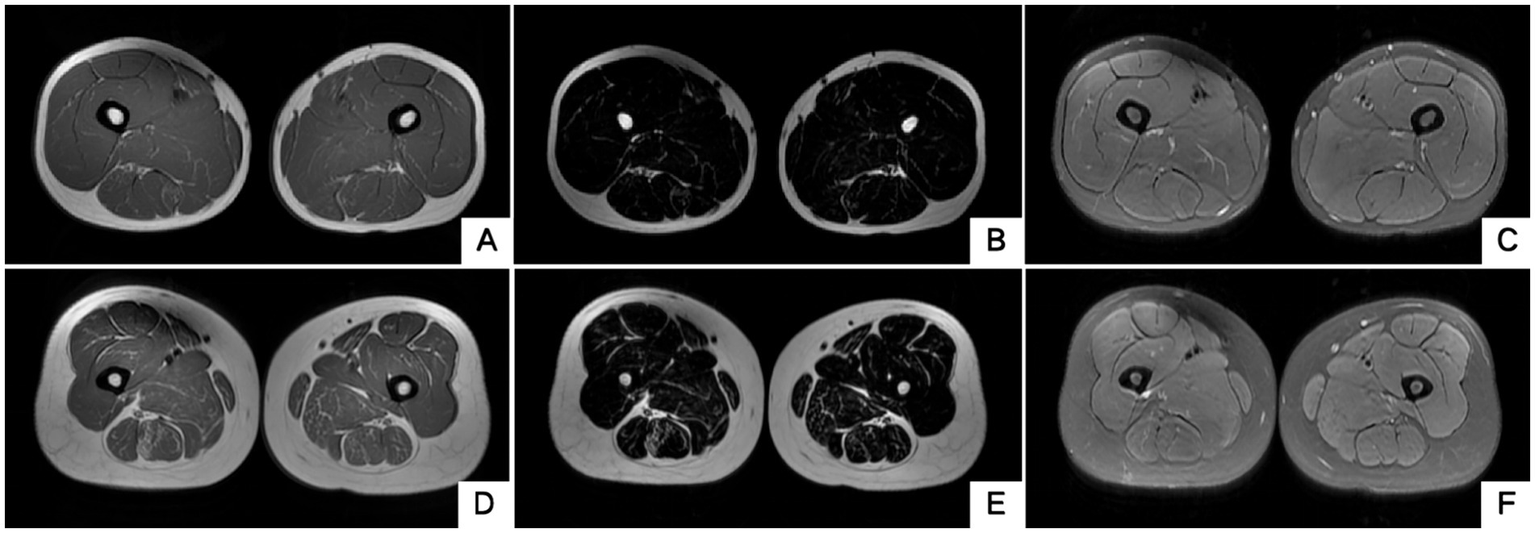

Figure 6

Muscle MRI of two probands’ thighs. No anomalies found. MRI of both thighs were taken at the level that is approximately 25 cm above the knee. (A–C) Proband 1 III-5. (D–F) Proband 2 II-3. A/D, B/E and C/F are T1WI, T2 water suppression and T2 fat suppression, respectively.

The blood routine, thyroid function, liver and kidney function, electrolytes, and muscle enzymes of 2 probands were all normal (see Figure 3). Family 1 members’ electrocardiogram showed no obvious abnormalities, and X-rays of both hands revealed bilateral fifth-digit clinodactyly (see Figure 4A). The proband’s electrocardiogram in Family 2 showed sinus rhythm, frequent premature ventricular contractions, and bigeminy (see Figure 5), and X-rays of both hands showed flexion deformity in the index finger joint of the left hand (see Figure 4B). The spinal X-ray of two probands revealed mild scoliosis (see Figures 4C,D). Echocardiography and muscle MRI showed no significant abnormalities (see Figure 6). Neurophysiological examinations of the 2 probands: Needle electromyography and nerve conduction were normal. The long exercise test showed a 58 and 65% reduction in left ulnar nerve CMAP amplitude after 10 min of exercise, indicating a positive result.